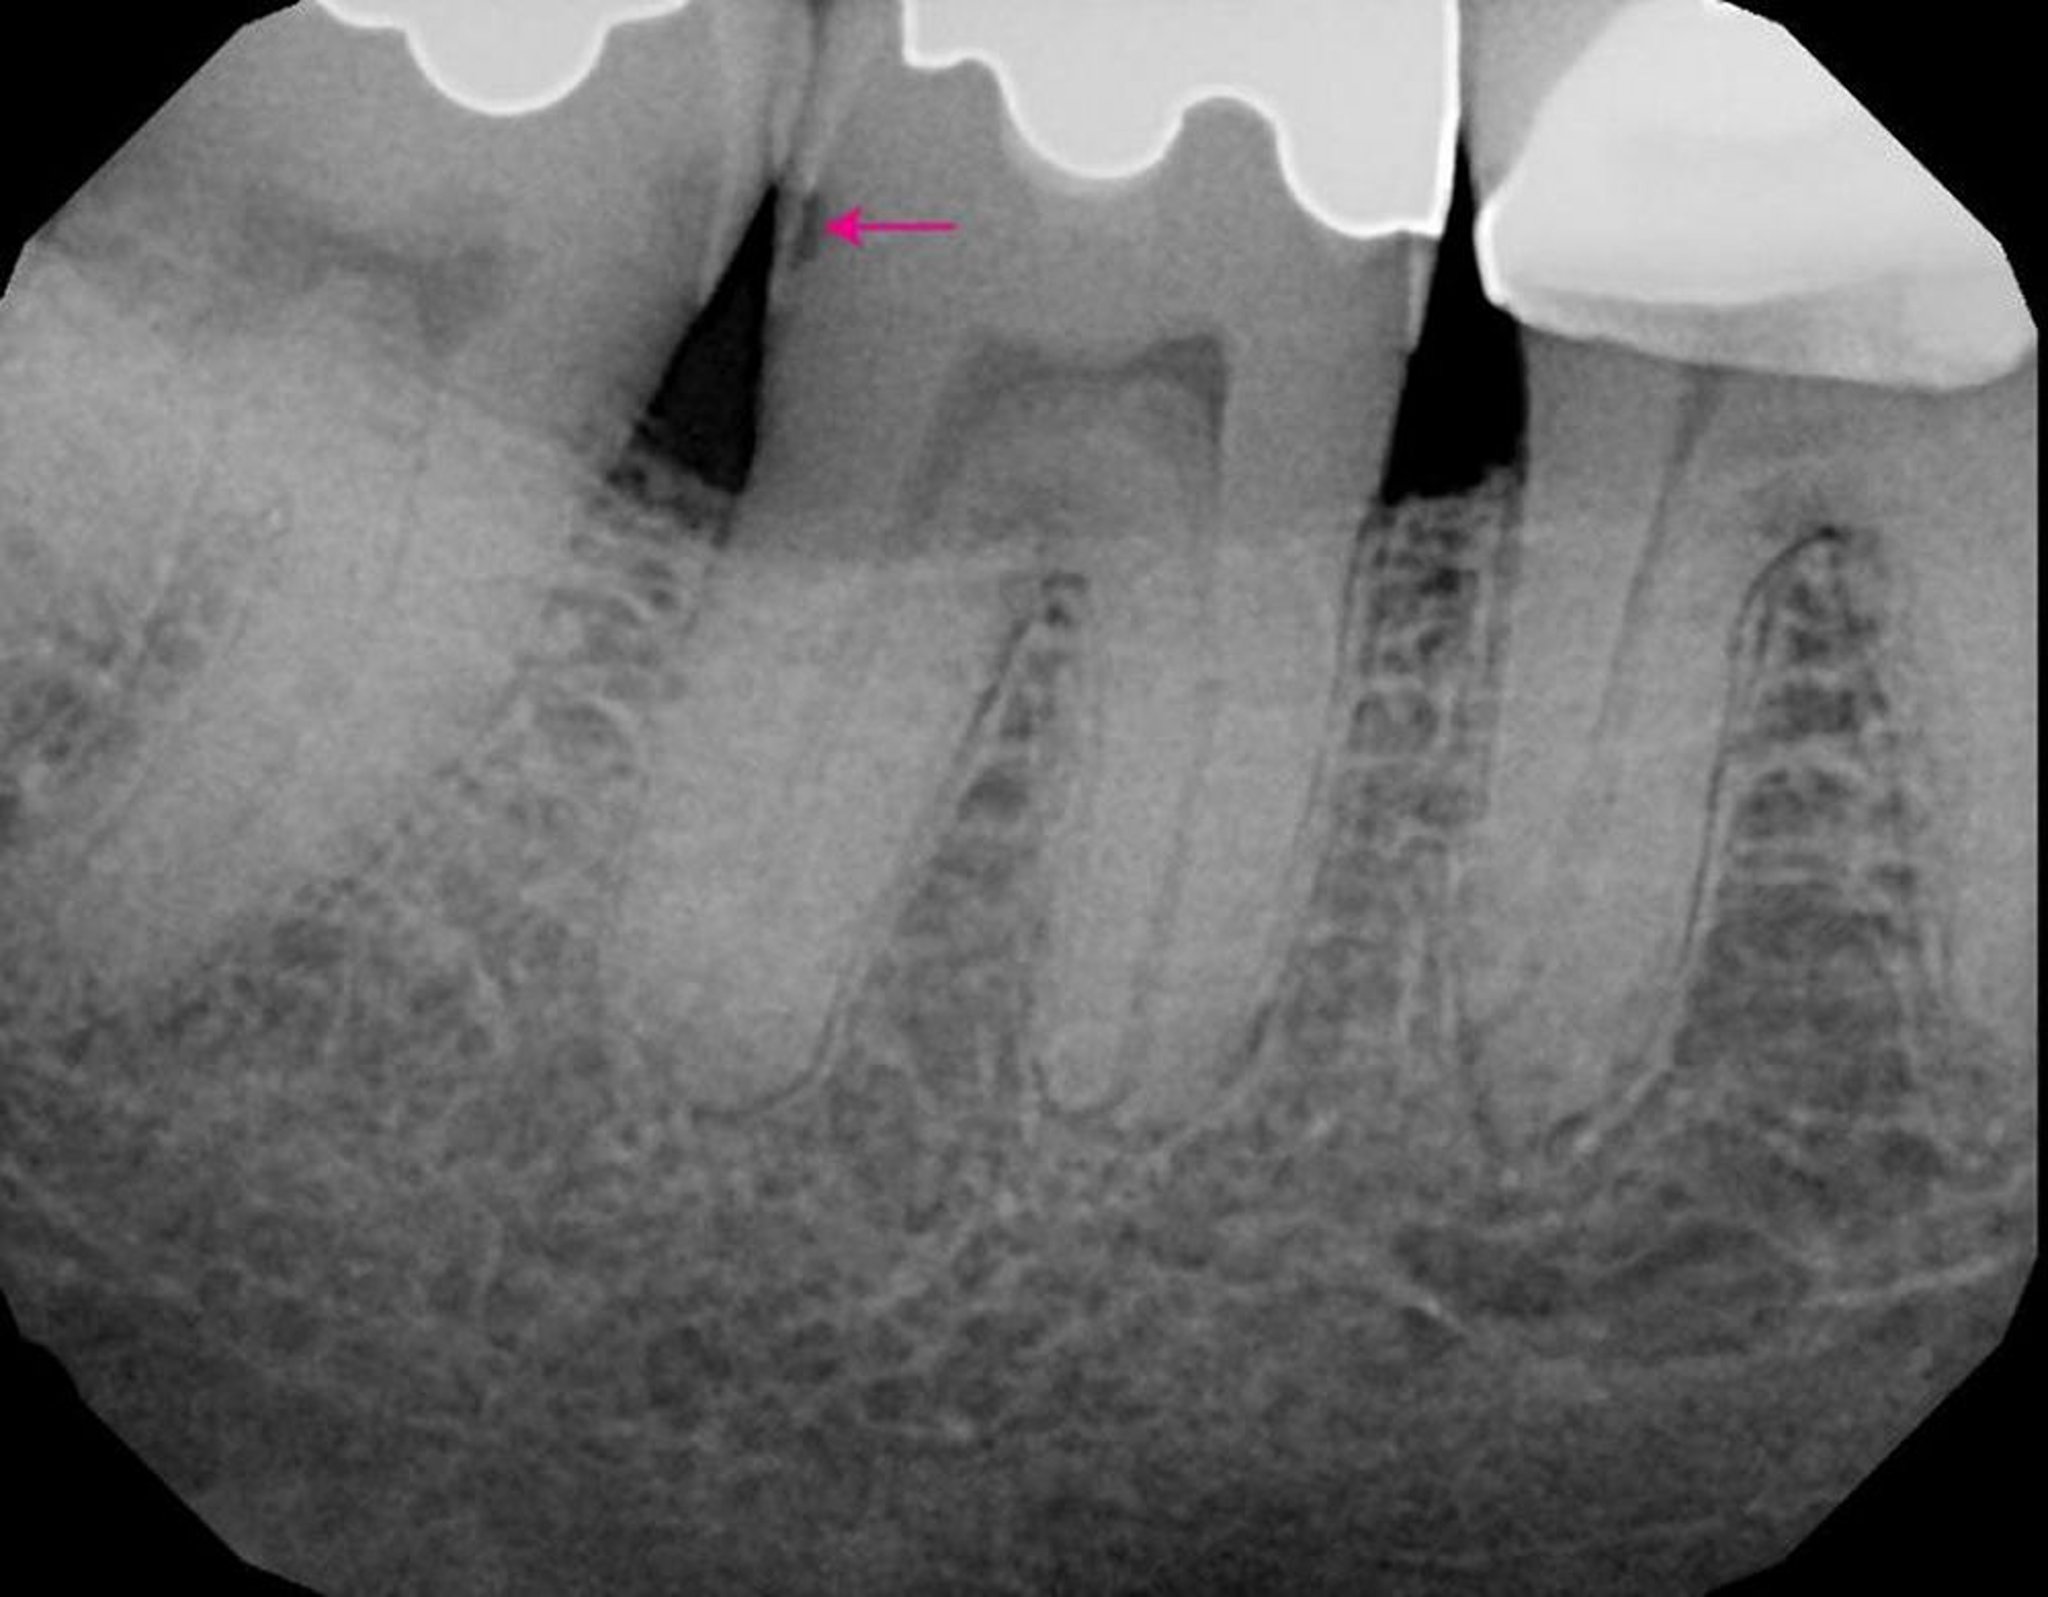

齲蝕の診断

• 直接視診と歯科用探針の慎重な使用

• 定期的な歯科X線検査

• ときに特殊な補助検査

定期的かつ頻繁な臨床的評価(歯科医師により評価された患者の齲蝕のリスクに応じて3~12カ月毎)を行えば,早期に齲蝕を同定し,最小限の介入で進行を阻止できる。細い探針,ときに特別な色素,および光ファイバーによる透視法が用いられ,まれではあるが,電気伝導度,レーザーの反射率,または透過光の変化によって齲蝕を検出する新しい装置もそれらを補完するものとして使用されている(近赤外線を用いた装置の使用を含む)。しかしながら,X線検査は依然として齲蝕の発見と進行度の判定,および既存の修復物の下にある齲蝕の同定に最も重要な役割を果たす。